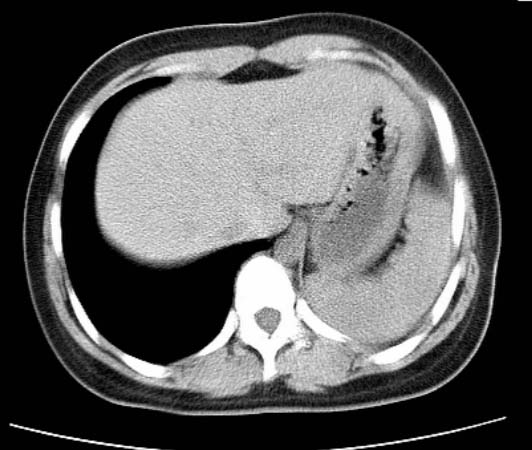

标题: CT25648:求教:是肺发育不全还是结核?

女  20岁。一月前咳血,诊“肺结核”抗痨治疗一月后,咳血停止,现复查。病人精神好。前后ct片对比未见明显变化。既往体检“正常”

1)考虑左肺结核并肺不张、支气管扩张。2)纵隔疝。

考虑左肺结核,左肺毁损,纵膈左偏,既往体检正常不可靠,tb一个月也不会这个样子的,有钙化,应该病程较长,冰冻三尺非一日之寒!